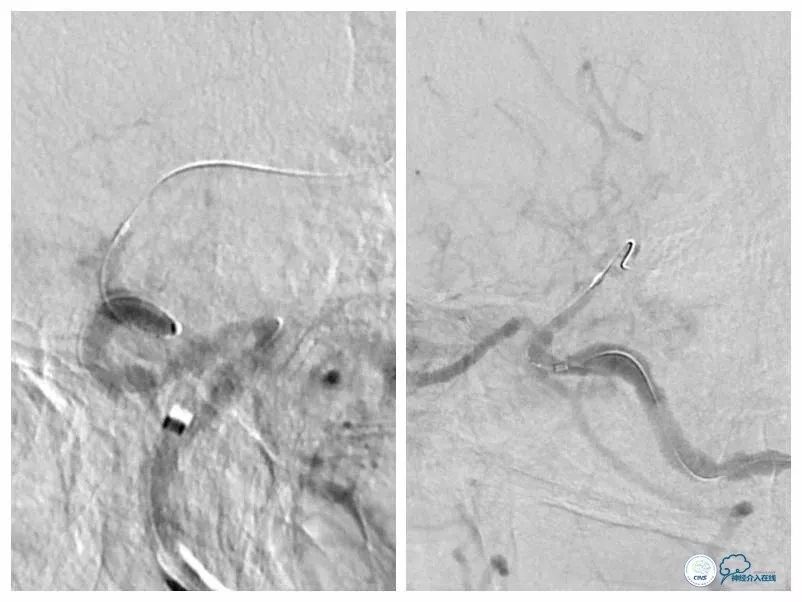

本例患者狭窄程度较硬,微导丝通过病变后但微导管无法跟进,由于首过病变的微导丝系200cm短导丝,遂只能采用分节剪短微管方法撤出微导丝(图17)。

图17

此外受限微导丝长度,也不能使用自膨支架。所幸,使用8F导引导管+6F Navien导管,系统支撑性较强,两枚Apollo支架均能到位,才得以顺利完成治疗。术后患者出现眼动脉栓塞症状,予以处理后病情缓解,目前电话随访患者眼部症状消失。